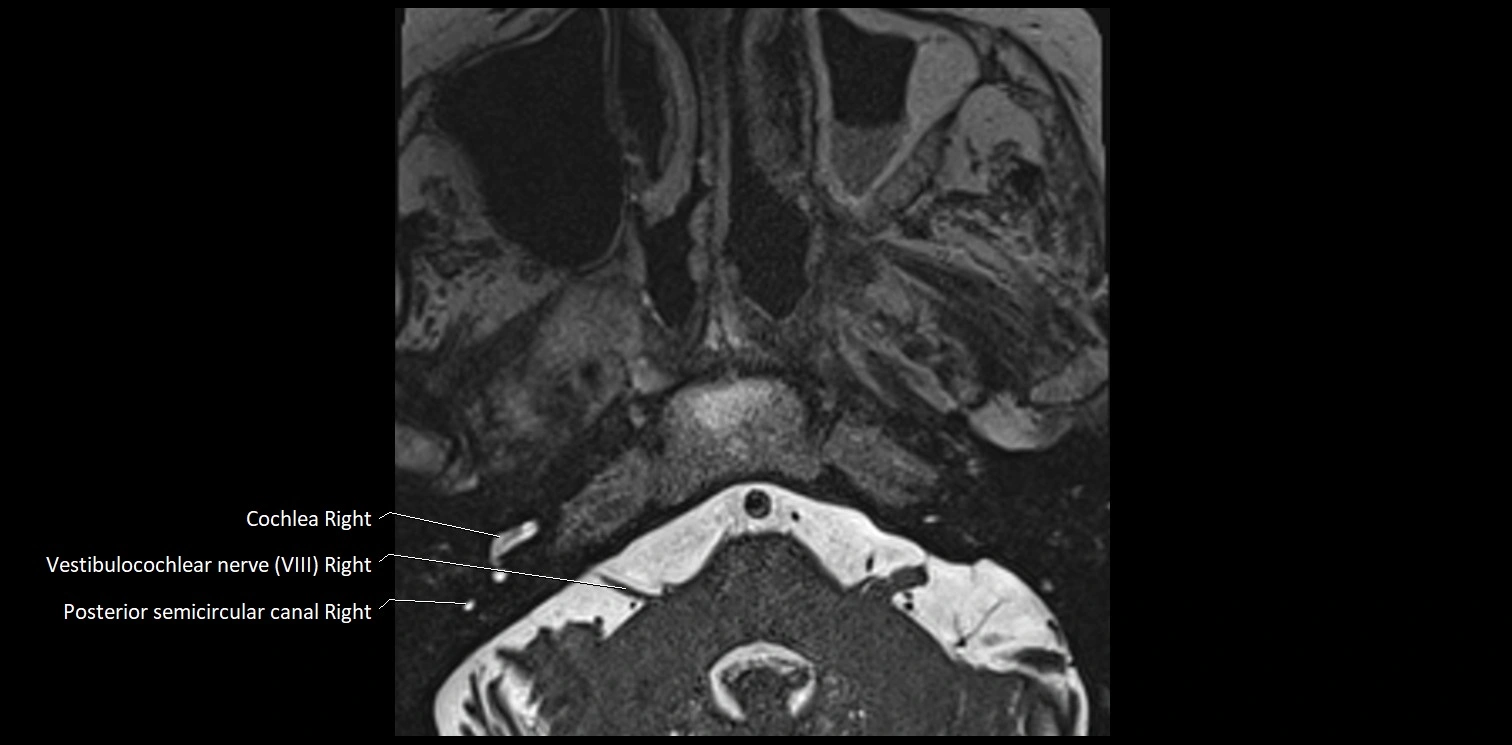

MRI Appearance

• The abducens nerve is a small, thin, linear structure

• Best visualized on high-resolution T2-weighted 3D MRI sequences (e.g., FIESTA or CISS)

• Seen as a hypointense (dark) line running from the brainstem at the pontomedullary junction, traversing the prepontine cistern, and entering Dorello’s canal under the petrosphenoidal ligament, then into the cavernous sinus, and finally the orbit

• May be challenging to visualize in standard MRI due to its small size

• Pathology may be inferred by absence, displacement, or enhancement of the nerve

MRI images

image